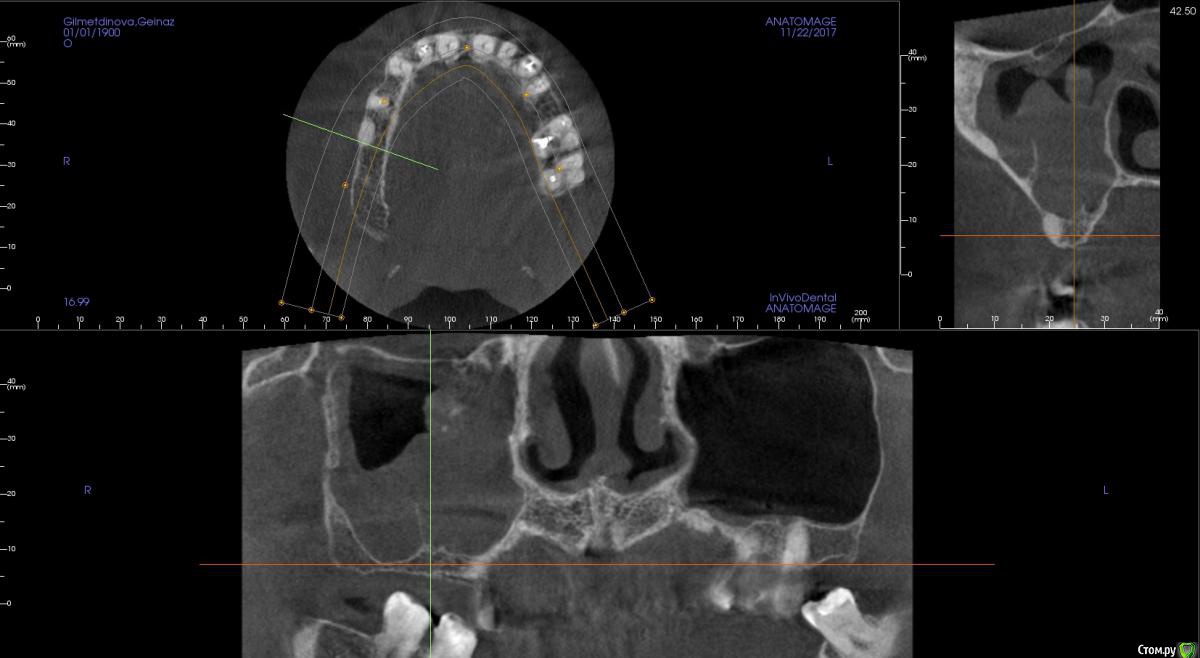

kamranchick Опубликовано 16 апреля, 2018 Автор Поделиться Опубликовано 16 апреля, 2018 Смотрел, и такое заключение дал. вот меня и смутило, в верхней трети около соустя вообще вкрапления какие то есть )) Ссылка на комментарий

Irouil Опубликовано 16 апреля, 2018 Поделиться Опубликовано 16 апреля, 2018 Смотрел, и такое заключение дал. вот меня и смутило, в верхней трети около соустя вообще вкрапления какие то есть ))Больше всего похоже на грибковое тело, и вкрапления эти намекают, и контуры затенения. Пунктировать не стал ЛОР это? 1 Ссылка на комментарий

kamranchick Опубликовано 16 апреля, 2018 Автор Поделиться Опубликовано 16 апреля, 2018 Больше всего похоже на грибковое тело, и вкрапления эти намекают, и контуры затенения. Пунктировать не стал ЛОР этоОтправил для санации, он написал вот это только( что ретенционная, но потом я внимательно начал крутить туда сюда и вот засомневался Ссылка на комментарий

Irouil Опубликовано 16 апреля, 2018 Поделиться Опубликовано 16 апреля, 2018 По большому счету; какая разница то? Вы же пациентку ради синус лифта (насколько я понимаю) отправляли, в таких условиях его не сделать. Там даже если соустье толщиною с пенис Трампа будет, все равно его ткани+отек перекроют после синуса. Так или иначе пазуху надо оперировать, только если ЛОР не считает что ретенционная киста - одонтогенная и пройдет при санации первичного очага) Ссылка на комментарий